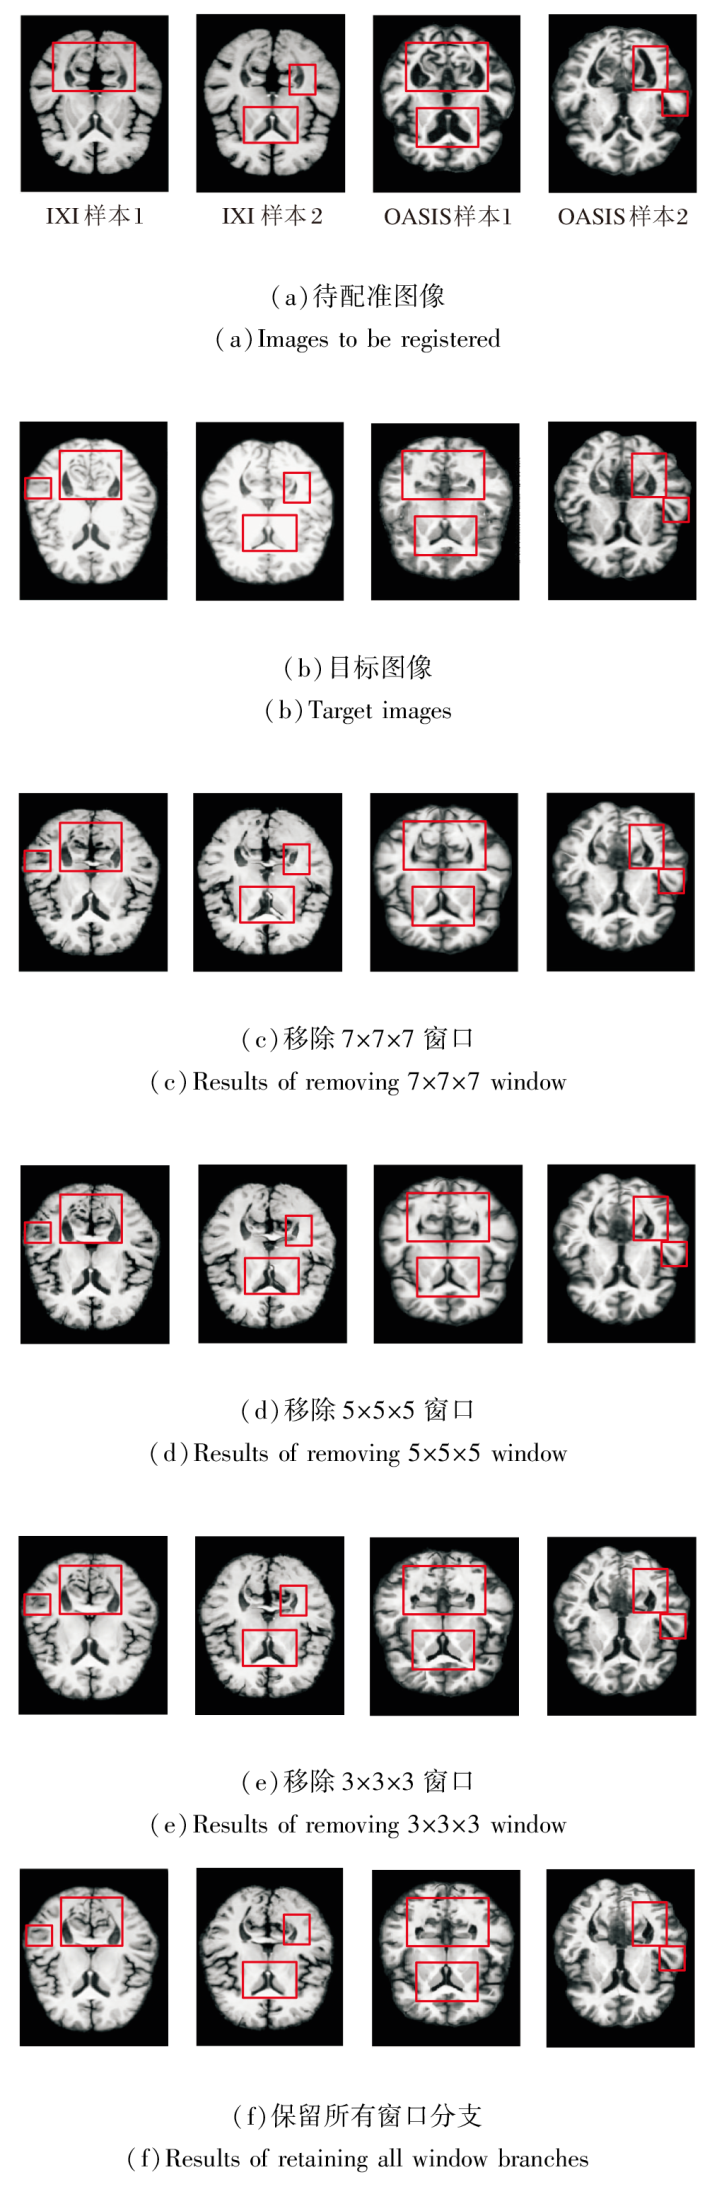

2.7.2 组件级消融实验

CMW-MLP采用多窗口设计, 分别捕获细粒度、中等尺度与大尺度的空间特征.为了验证该设计的有效性, 以包含全部3个窗口(3× 3× 3、5× 5× 5和7× 7× 7)的PyraMLP-Net为基准, 分别移除其中一个窗口, 在相同实验设置下分析各窗口对捕捉不同尺度形变的贡献.

在IXI、OASIS数据集上各选取2个样本, 分别移除其中一个窗口后的图像配准结果如图15所示, 对PyraMLP-Net性能的影响如图16所示.由图可见, 当分别移除7× 7× 7窗口、5× 5× 5窗口、3× 3× 3窗口时:PyraMLP-Net在IXI数据集上的DSC值分别下降约1.3%、1.8%和0.6%, HD95值分别上升约9.3%、11.7%和4.2%; 在OASIS数据集上, DSC值相应降低1.4%、1.7%和0.9%, HD95值相应提升8.1%、9.3%和3.5%.这一结果表明, 任意一种窗口的缺失都会导致PyraMLP-Net的配准精度下降, 由此凸显多窗口协同的有效性.

造成这一现象的原因在于不同尺寸窗口建模的变形尺度及其在脑图像中的分布存在差异.5× 5× 5窗口专注于捕捉中等范围的局部变形, 这类变形在脑部结构中占比最高, 对整体配准精度影响最显著, 因此移除该窗口导致的性能损失最大.

7× 7× 7窗口用于感知较大尺度的局部变形, 该类变形在图像中虽存在但占比低于中等变形, 故移除7× 7× 7窗口后精度损失次之.3× 3× 3窗口主要捕捉细微解剖结构的局部位移, 对配准精度贡献相对较小, 因此移除时性能下降幅度最小.上述结果说明, 只有整合多尺度窗口的感知能力, 才能全面覆盖不同范围的依赖关系, 实现最优的配准精度, 也进一步验证CMW-MLP中多窗口协同架构设计的合理性与必要性.